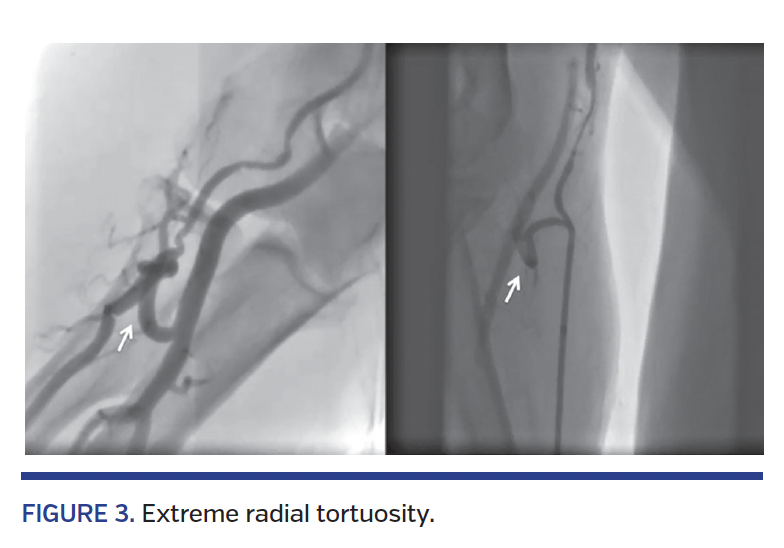

Details of the obstacles/anomalies are provided in Table 3. Radial spasm was the most commonly encountered obstacle (n = 72; 2.8%) followed by subclavian tortuosity (n = 56; 2.2%) (Figures 1 and 2). Extreme radial tortuosity and radial loops were very uncommon (<1%) (Figures 3 and 4).

Success rates with individual obstacles/anomalies are provided in Table 4. Most of the obstacles/anomalies were successfully negotiated; however, extreme radial tortuosity and radial loops had relatively lower success rates (18% and 20%, respectively). Some of the radial loop and extreme radial tortuosity cases were negotiated successfully with the use of 0.35˝ hydrophilic wires or 0.014˝ angioplasty wires (Figure 5). Subclavian tortuosity and stenosis accounted for 58 cases (2.3%) (Figures 2 and 6). Of these, 73% were successively negotiated with the use of hydrophilic wires and/or breath-holding maneuvers, which helped in straightening the loop (Figure 7). Two of the subclavian tortuosity cases were arteria lusoria (retroesophageal course of the subclavian artery); in both cases, we failed to negotiate and had to switch to femoral access.